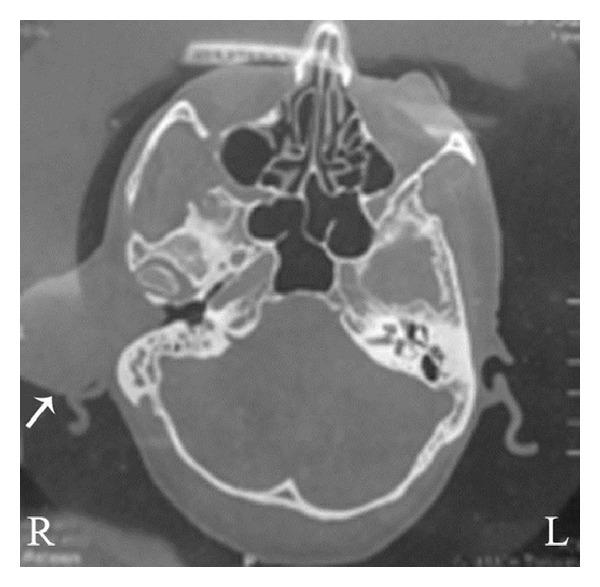

Retiform hemangioendothelioma is a rare intermediate or borderline neoplasm of the blood vessels that mostly occurs in extremities. Here we report a unique case of retiform hemangioendothelioma presented in the external auditory canal. 58-year-old male patient presented with the complaint of right ear swelling for 4 years. On examination, a spherical swelling in the right ear was found occluding the view of external auditory canal. The tumor was removed surgically. Intraoperatively, the mass was found attached to the outer part of the right external auditory canal near the root of helix. Histopathology of the resected tumor showed typical features of retiform hemangioendothelioma. In addition, immunohistochemical analysis revealed that tumor was positive for endothelial cell marker CD34 and occasionally positive for cell proliferative marker Ki-67.

网状血管内皮瘤是一种罕见的血管中间型或交界性肿瘤,主要发生于四肢。本文报告1例发生于外耳道的罕见网状血管内皮瘤。一名58岁男性患者因右耳肿胀4年就诊。检查发现右耳有一球状肿物,阻塞外耳道视野。手术切除肿瘤。术中发现肿物附着于右外耳道靠近耳轮根部的外侧部分。切除肿瘤的组织病理学检查显示为典型的网状血管内皮瘤特征。此外,免疫组化分析显示肿瘤内皮细胞标志物CD34阳性,细胞增殖标志物Ki-67偶尔阳性。